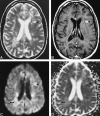

<sc>fig</sc> 2.

fig 2.

Example of an HEL in a patient with MS. A–D, Axial T2-weighted image (4000/110/1) (A), contrast-enhanced T1-weighted image (500/20/1) (B), isotropic diffusion-weighted image (4000/125/1) (C), and trace ADC map (D) show a T1-weighted HEL (arrow), which shows increased diffusion on the trace ADC map.